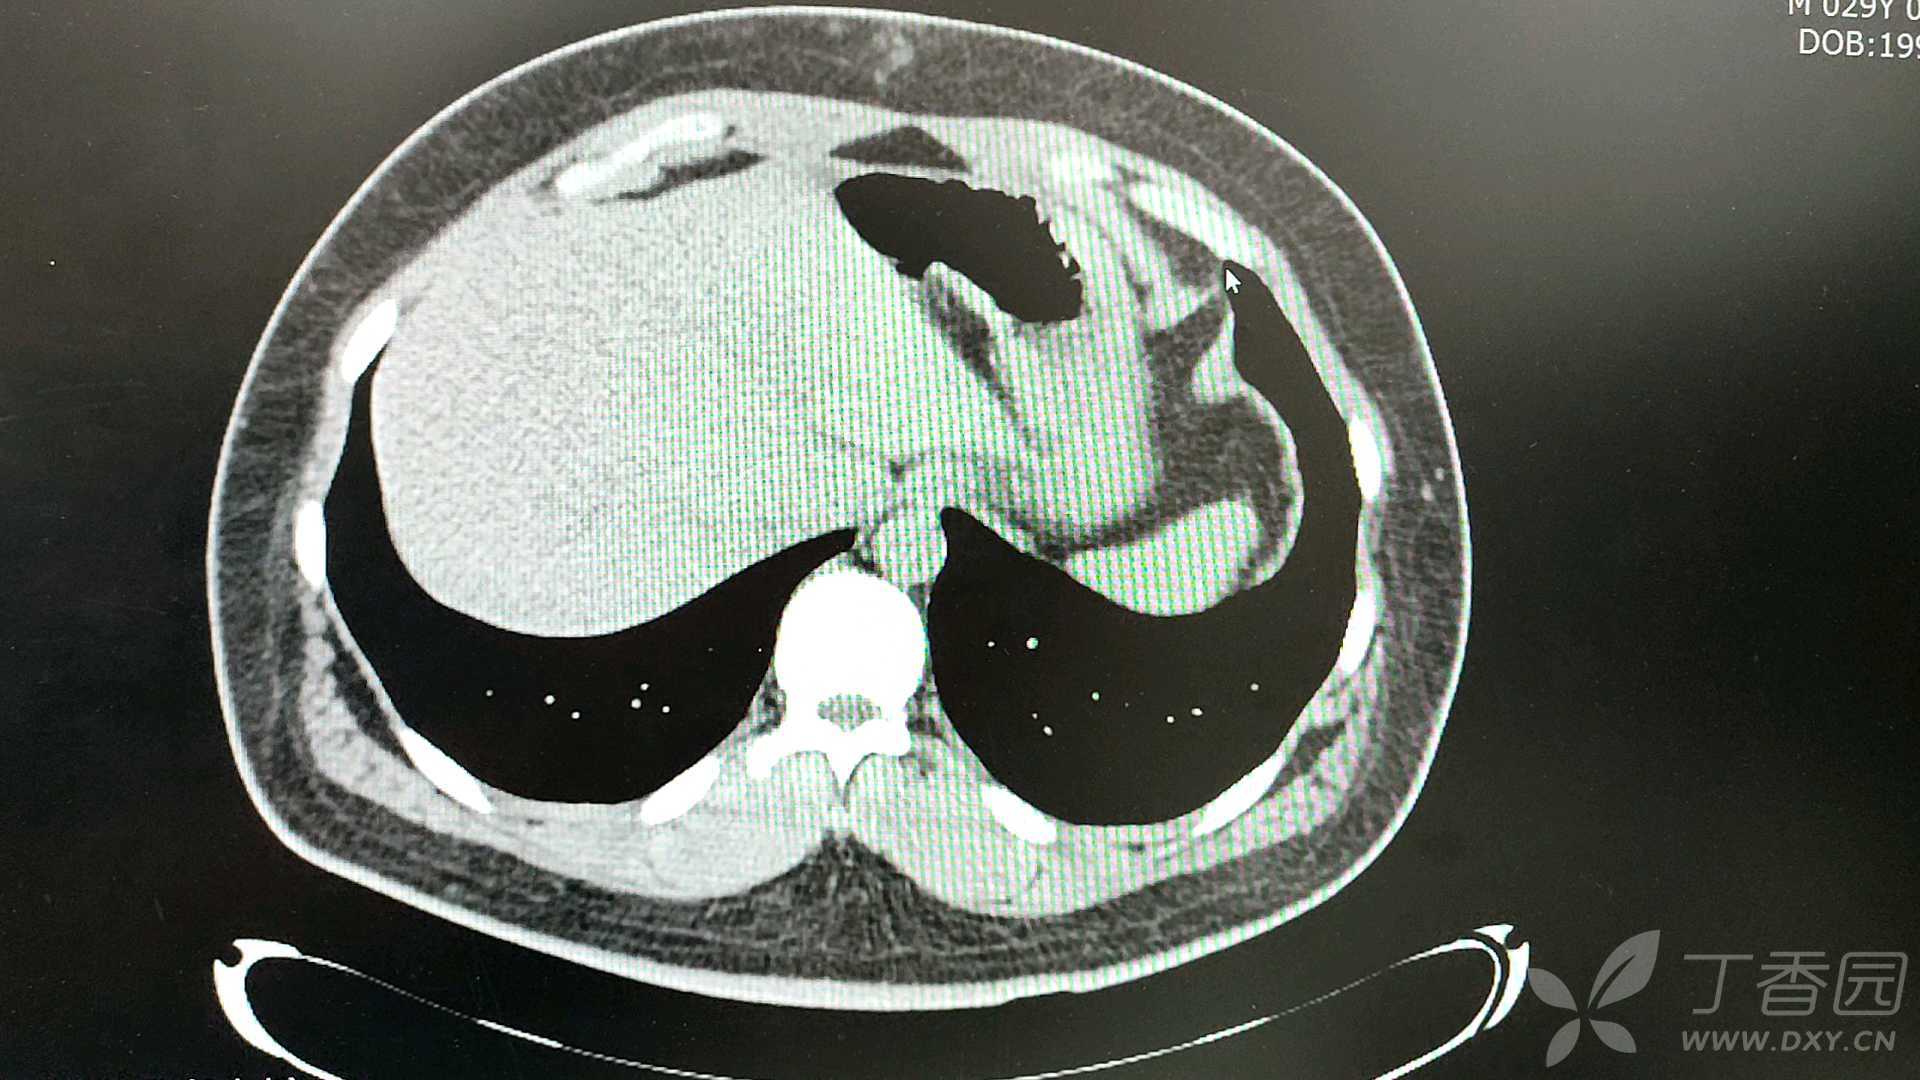

同门师兄,行胆囊摘除术后一个月,

仍然无法回到工作岗位,

进食过多,或荤腥油腻,

原胆囊部位,还是会疼痛。

CT(水平面) 如下: